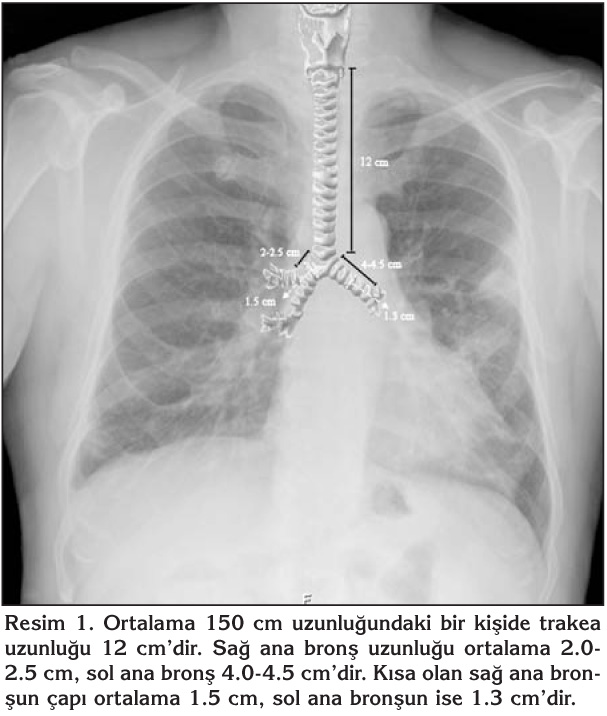

Hastaya uygun ?LT boyutunun saptanmas?nda, ?e?itli y?ntemler kullan?lmaktad?r. Bunlarda bir tanesi direkt sol bron? geni?li?inin ?l??lmesidir (7). Sol ana bron? geni?li?inin ?l??lmesinde, posteroanterior akci?er grafisi (%50-75) ve toraks tomografisinden yararlan?labilir (Resim 3) (8,9). ?LT boyutunun se?iminde cinsiyet ve boy uzunlu?u dikkate al?nmal?d?r (Tablo 2). Tablo 3'te ?LT boyutlar?, birlikte kullan?lmaya uygun fiberoptik bronkoskop boyutlar? ve ?LT'ler ile tek l?menli ETT'lerin i?i ve d?? ?aplar? kar??la?t?r?lm??t?r. Tablodan da g?r?ld??? gibi ?LT'lerde d?? ?ap, i? ?apa oranla daha b?y?k oldu?u i?in vokal kordlardan ge?i?te zarar verip postoperatif d?nemde ses k?s?kl??? ve bo?az a?r?s?na neden olabilmektedir (10).

Resim 3